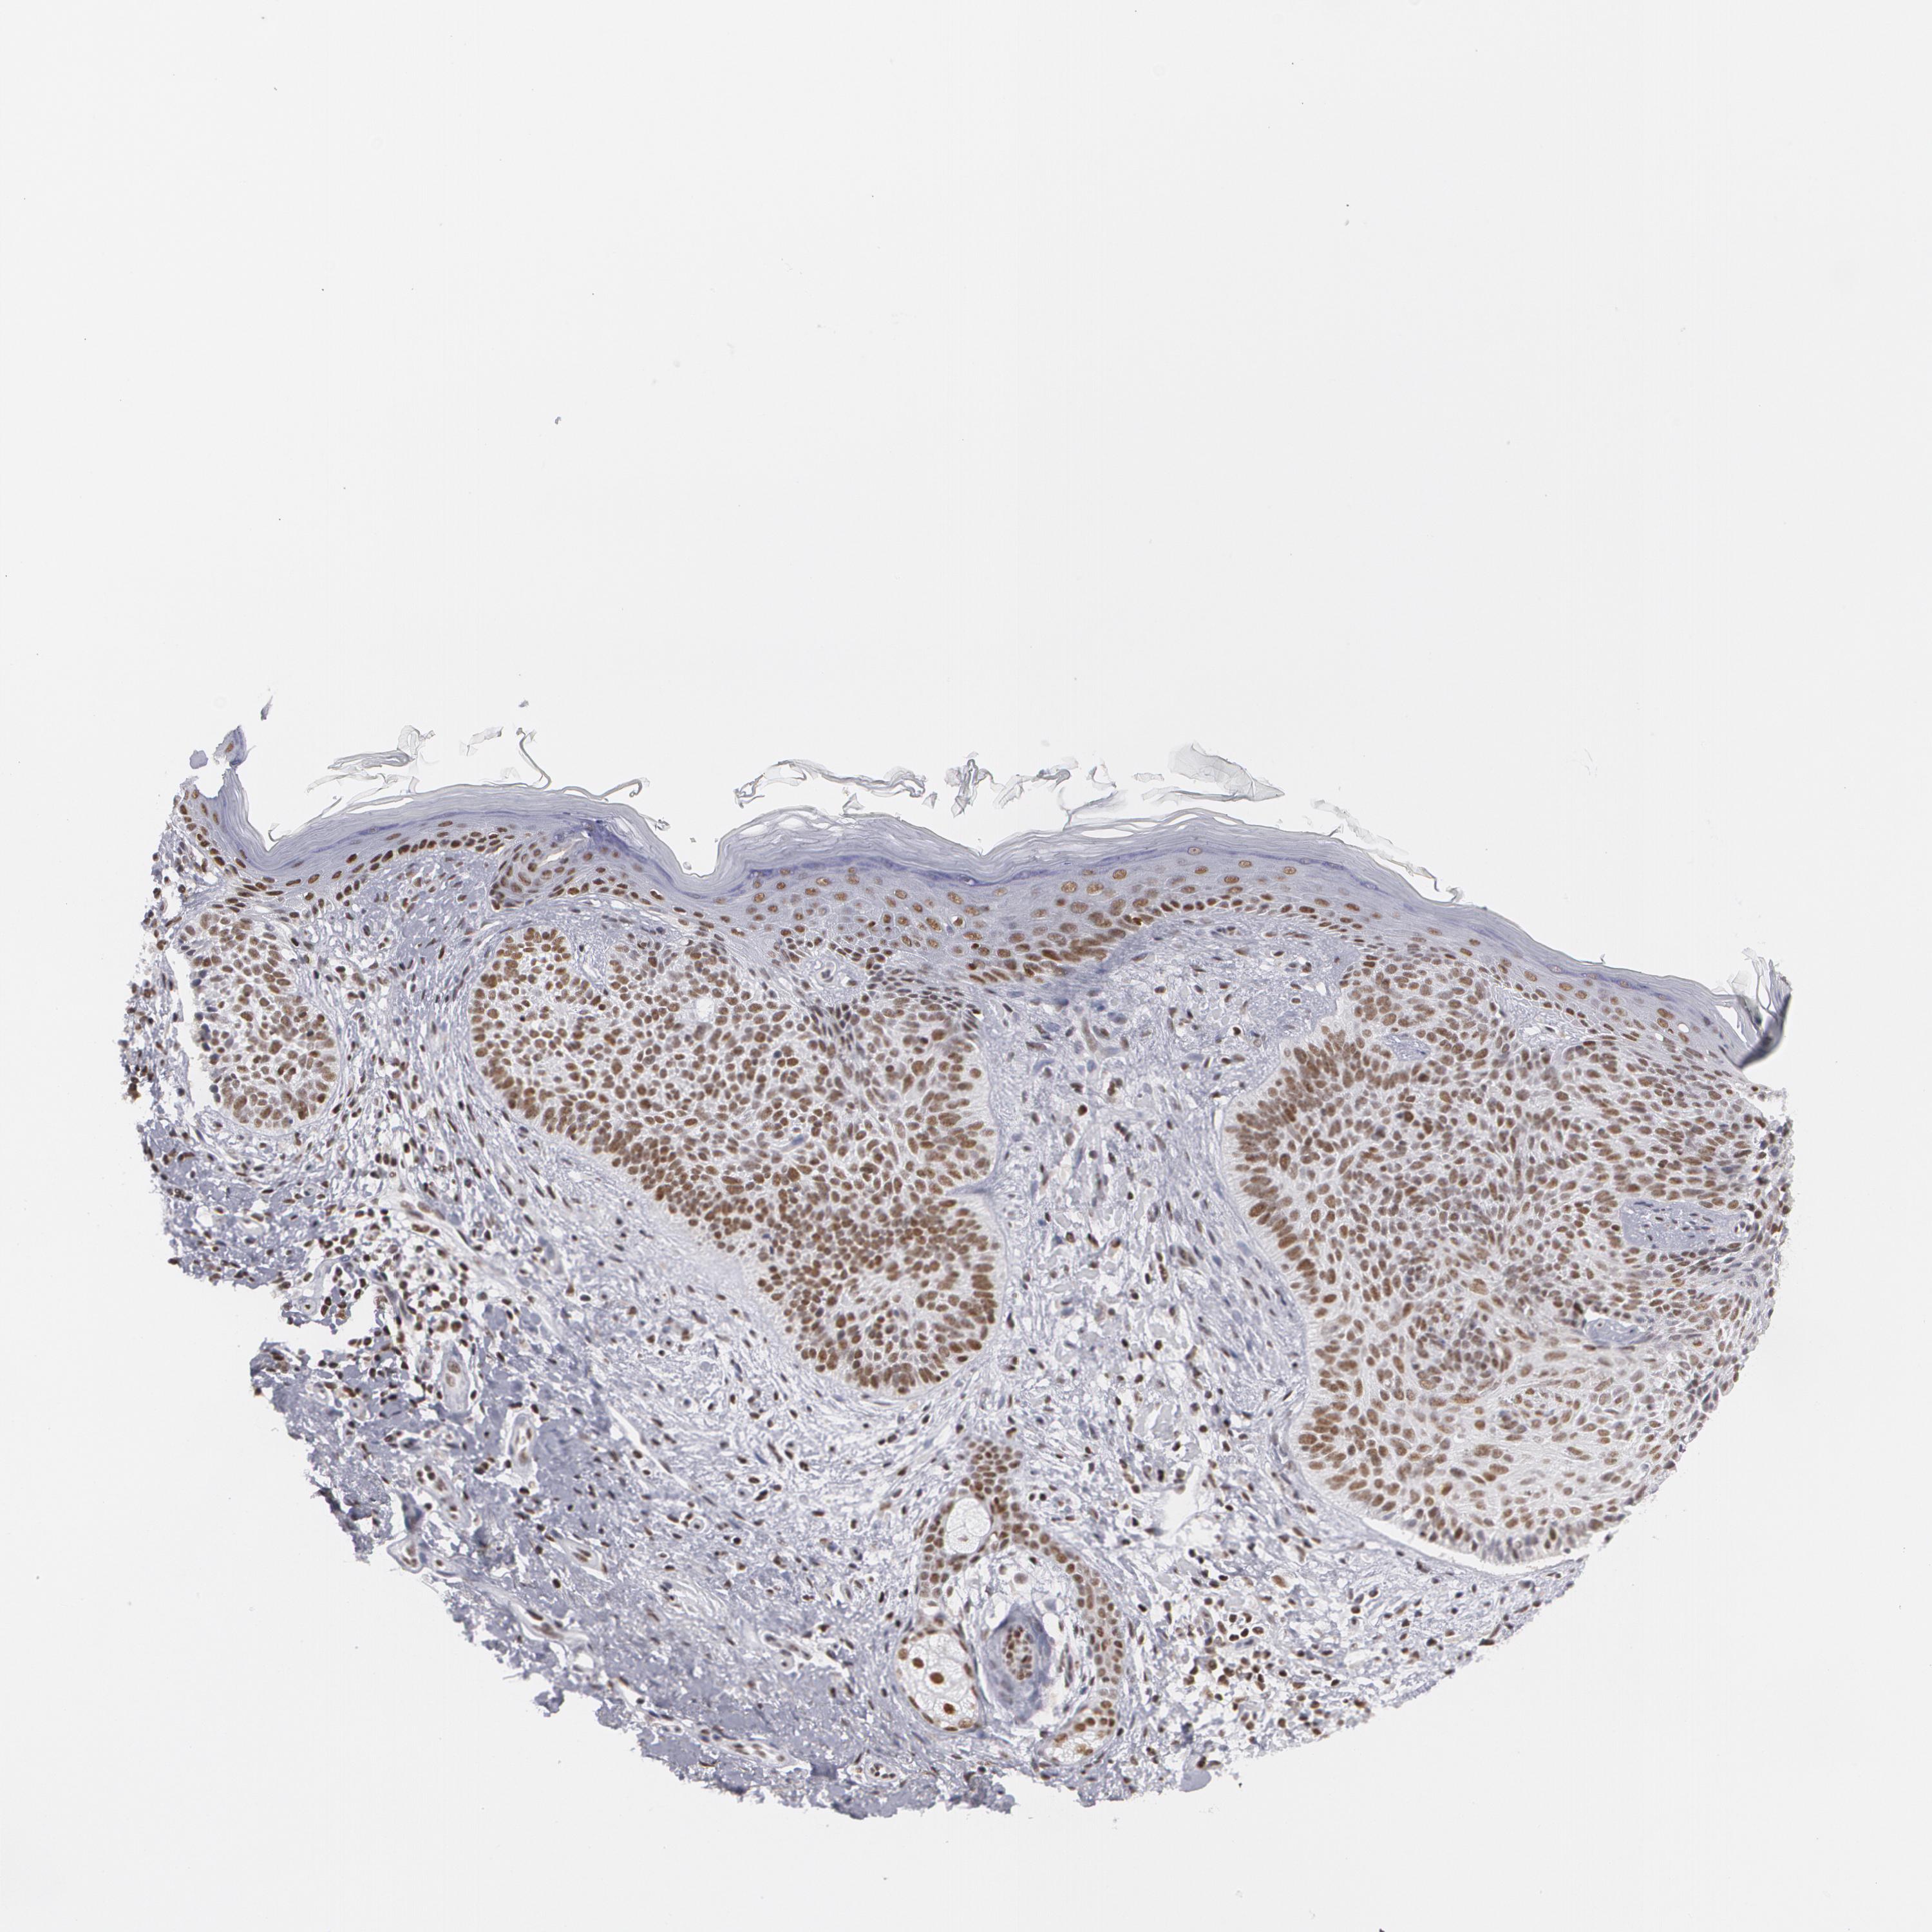

CANCER SKIN CANCER Show tissue menu

Basal cell and squamous cell cancer

SKIN CANCER - Protein expressioni

A mouse-over function shows sample information and annotation data. Click on an image to view it in a full screen mode. Samples can be filtered based on level of antibody staining by selecting one or several of the following categories: high, medium, low and not detected. The assay and annotation is described here.

Antibody stainingi

Antibody staining in the annotated cell types in the current human tissue is reported as not detected, low, medium, or high, based on conventional immunohistochemistry profiling in selected tissues. This score is based on the combination of the staining intensity and fraction of stained cells.

Each image is clickable and will lead to virtual microscopy that enables deeper exploration of all samples and also displays staining intensity scores, fraction scores and subcellular localization as well as patient and tissue information for each sample.

Antibody HPA008455

Antibody HPA031125

Antibody CAB002781

Antibody CAB068195

Squamous cell carcinoma, NOS

Squamous cell carcinoma, metastatic, NOS

Basal cell carcinoma

Papilloma, NOS